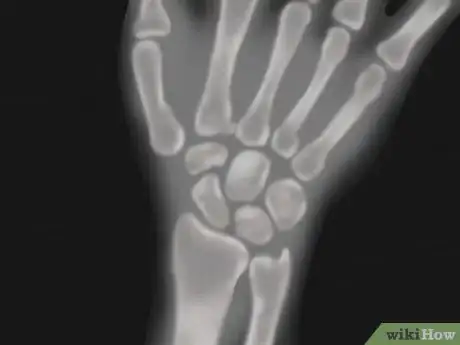

1See your doctor. In instances of significant wrist trauma that leads to severe pain, swelling, bruising, and/or loss of hand function, it's best to see your family physician or emergency department immediately so that the correct diagnosis can be made. Grade III wrist sprains involve completely severed ligaments, which will need surgery to repair.[14] Other serious wrist conditions that your doctor should consider are fractures, dislocations, inflammatory arthritis (such as rheumatoid arthritis or gout), carpal tunnel syndrome, infection, and severe tendonitis.

- X-rays, bone scans, MRI, and nerve conductance studies are modalities that your doctor may use to help diagnose your wrist issue. Your doctor may also send you for a blood test to rule out rheumatoid arthritis or gout.